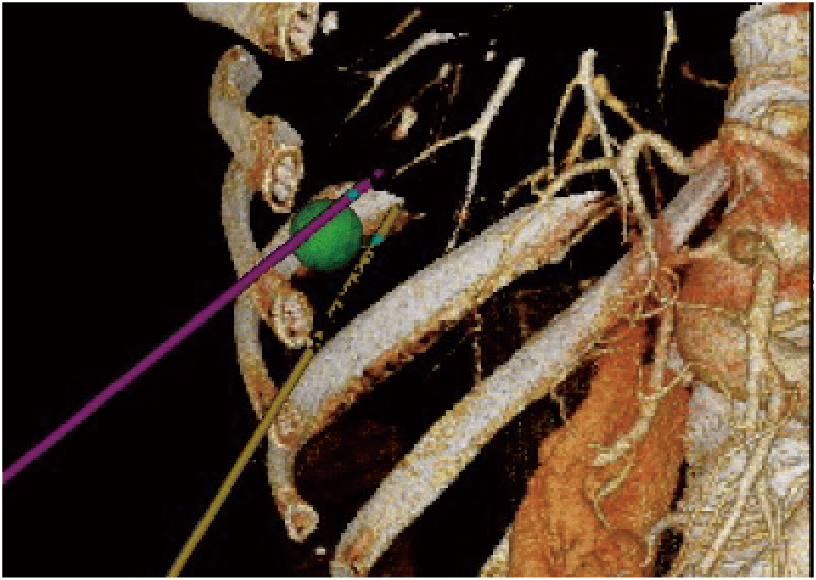

3 Boyutlu Sim-Navigatör / E-alan Simülatörü

Real-time Virtual Sonography (RVS) ile hedefe yönelim sırasında tek veya birden fazla iğne yolunun simülasyonunu sağlar. İşaretlenen hedef ve iğne yolları arasındaki konumsal ilişki, 3 boyutlu vücut işareti ve C düzlem ekranı kullanılarak gerçek zamanlı olarak değerlendirilebilir. Elektrikli Alan Simülatörü, elektrotların belirtilen konumundan gelen elektrikli alanı (E-alan), RFA tedavisi sırasında BT görüntüsünün üzerine bindirir. E-alanının simülasyonu, etkili bir iğne yolunun göz önünde bulundurulmasını sağlar.